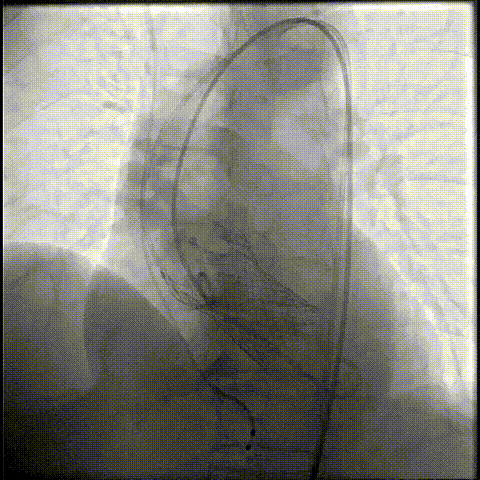

主动脉根部造影

初始定位